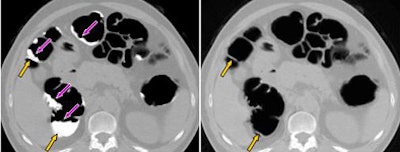

| Example of the cleansing results of a 9-mm polyp submerged in the tagged fecal materials in a clinical VC case by use of a previous threshold-based cleansing (T-cleansing) and a new structure-analysis cleansing (SA-cleansing) methods. (a) 3D volume-rendering view of the polyp after manual cleansing. (b) 3D view of the polyp in (a) after the application of T-cleansing. We observe the degradation of a fold (orange arrow) and a polyp (green arrow) as well as the creation of false fistula (red arrow). (c) 3D view of the polyp in (a) after the application of SA-cleansing. We observer no degradation of the fold (orange arrow) and the polyp (green arrow), as well as no creation of a false fistula. |

"Application on a CAD designed for nontagged (VC) shows that if applied after structure analysis cleansing was done, sensitivity increased from 40% to 80% compared to (threshold-based) cleansing, whereas the false-positive rate is reduced from 9.4 to 4.6 (per case) indicating that the subtraction or cleansing artifacts have been drastically reduced by this method," Yoshida said.

| Example of the cleansing results of a VC case with a large amount of semiliquid fecal materials by use of the new SA-cleansing method. Semiliquid fecal materials having rugged surfaces (violet arrows on the left image) are all removed whereas the submerged folds (orange arrows) are preserved. |

A submerged polyp shown as an example could not be seen in threshold-based cleansing, but was clearly visible after application of the structure-based algorithm, at which point it was visible to CAD as well, Yoshida said.